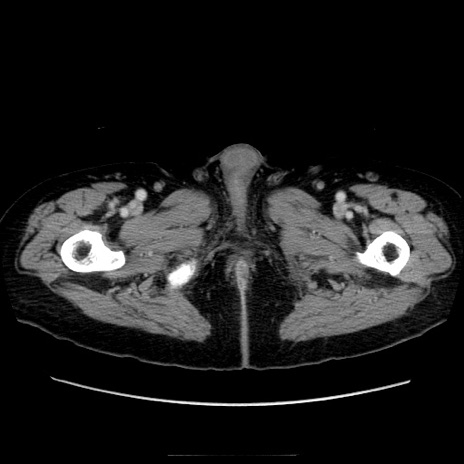

症例21(横断像)

【症例】70歳代男性

【主訴】腹痛

【現病歴】肝硬変・肝細胞癌にてかかりつけの方。約9時間前に食後より腹痛出現。症状が徐々に増悪し、嘔吐出現したため来院。

【既往歴】肝硬変、肝細胞癌(RFA、TACE後)

【身体所見】意識清明、表情苦悶様、BT 36℃、BP 129/78mmHg、P 88bpm、SpO2 97%(RA)、右上腹部から心窩部にかけて圧痛あり、反跳痛なし、筋性防御あり。

【データ】WBC 5800、CRP 0.16